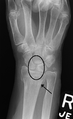

Stress view showing scapholunate instability